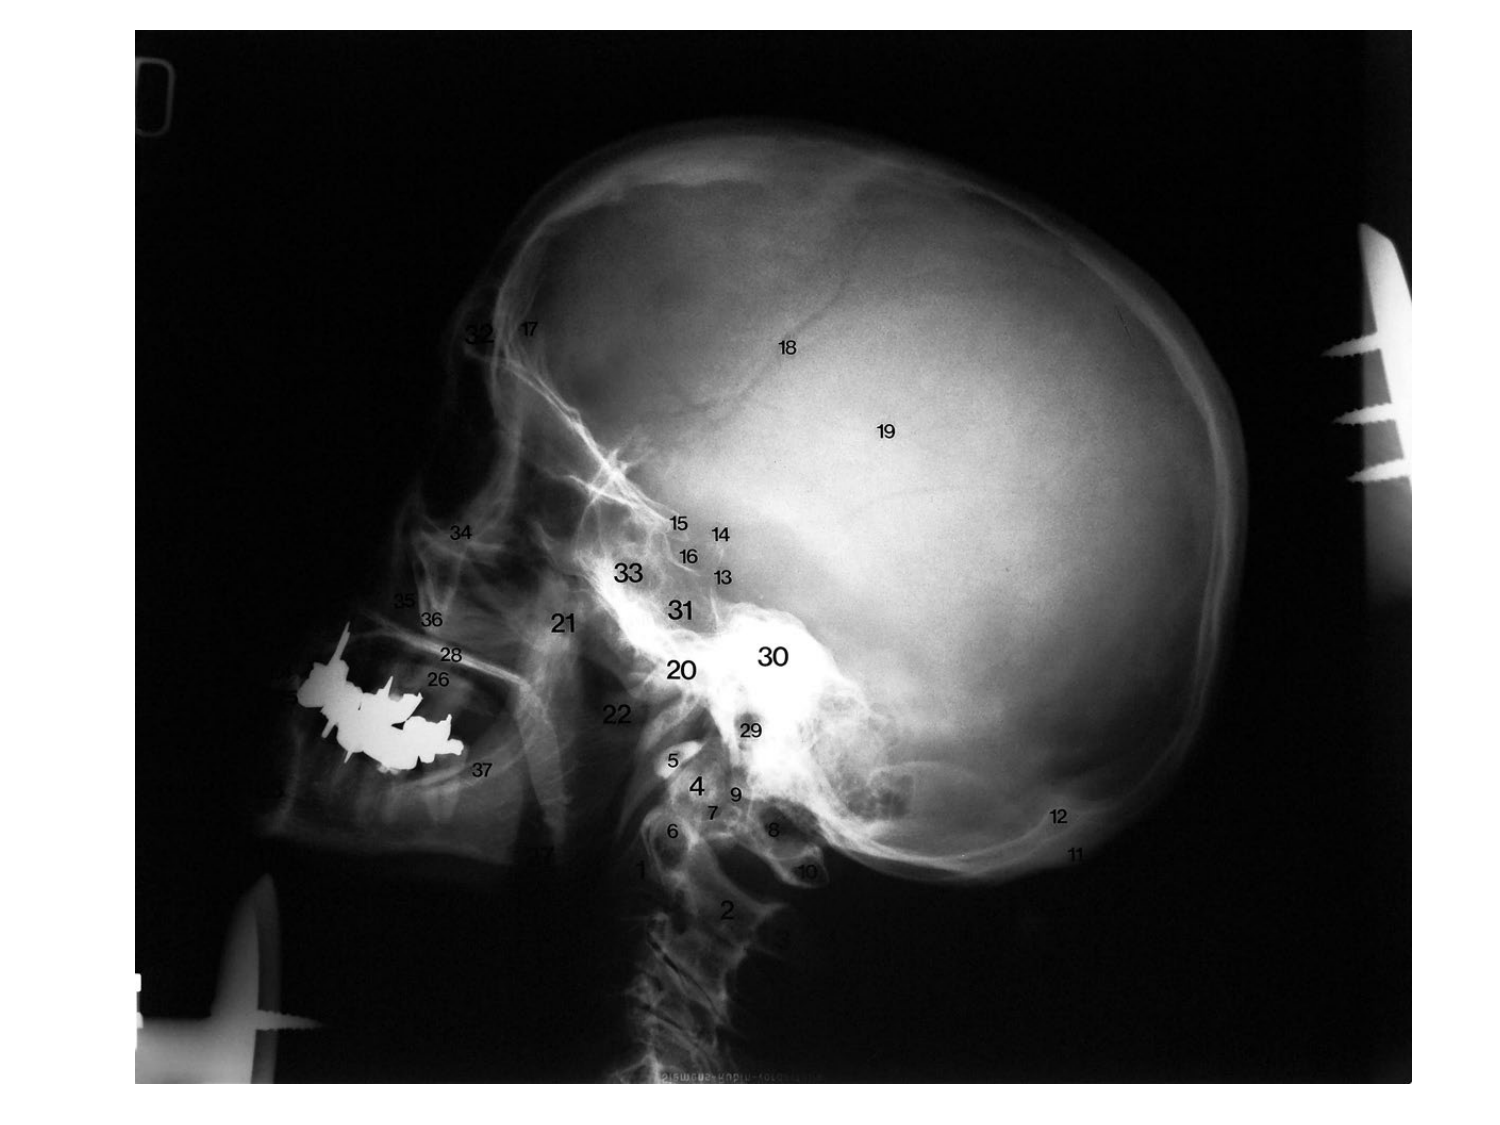

Anatomie du système endocrinien2

Bases de l'anatomie · 92 pages · 12 sections